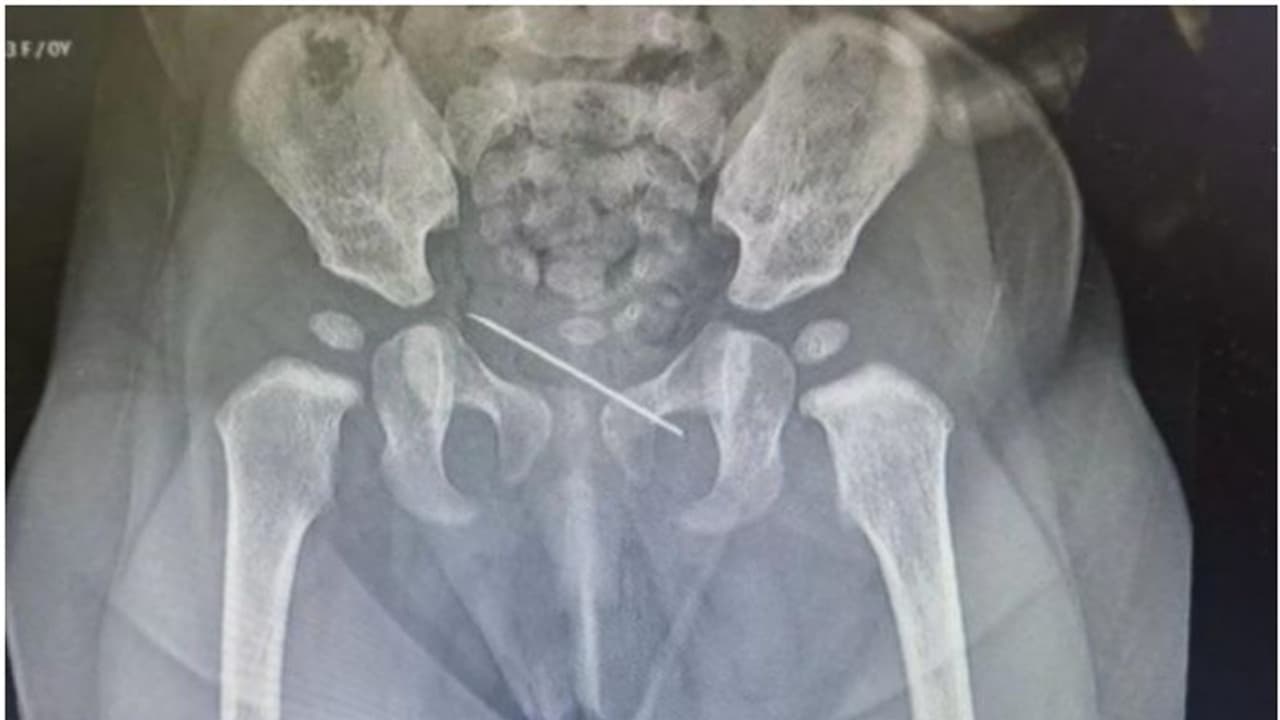

മനാമ: ഏഴു മാസം പ്രായമുള്ള കുഞ്ഞിന്റെ പെല്വിസില് നിന്നും സിറിഞ്ച് സൂചി പുറത്തെടുത്തു. അല് ഹിലാല് ഹെല്ത്ത് കെയര് ഗ്രൂപ്പാണ് കുട്ടിയുടെ ചികിത്സ വിജയകരമായി പൂര്ത്തിയാക്കിയത്. ബഹ്റൈനിലാണ് സംഭവം.

നാഭിയില് ചര്മ്മത്തിന് താഴെ അസാധാരണ വസ്തു അനുഭവപ്പെട്ടതിനെ തുടര്ന്നാണ് ഏഴു മാസം പ്രായമുള്ള പെണ്കുഞ്ഞിനെ മുഹറഖിലെ അല് ഹിലാല് ആശുപത്രിയിലെത്തിച്ചത്. സ്പെഷ്യലിസ്റ്റ് പീഡിയാട്രീഷ്യന് ഡോ. ഗൗതം എം ശിവാനന്ദയെ കാണാനെത്തിയ കുട്ടിയെ പരിശോധനക്ക് വിധേയമാക്കിയപ്പോഴാണ് 3.5 സെന്റീമീറ്റര് നീളത്തിലുള്ള സിറിഞ്ച് സൂചി കണ്ടെത്തിയത്.

തുടര്ന്ന് കുഞ്ഞിന്റെ സുരക്ഷ ഉറപ്പാക്കി കൊണ്ട് ലോക്കല് അനസ്തേഷ്യ നല്കി സിറിഞ്ച് സൂചി വിജയകരമായി പുറത്തെടുത്തു. ശസ്ത്രക്രിയ വിജയകരമായതിനെ തുടര്ന്ന് കുഞ്ഞിനെ ആശുപത്രിയില് നിന്ന് ഡിസ്ചാര്ജ് ചെയ്തതായി ആശുപത്രി അധികൃതര് അറിയിച്ചു.